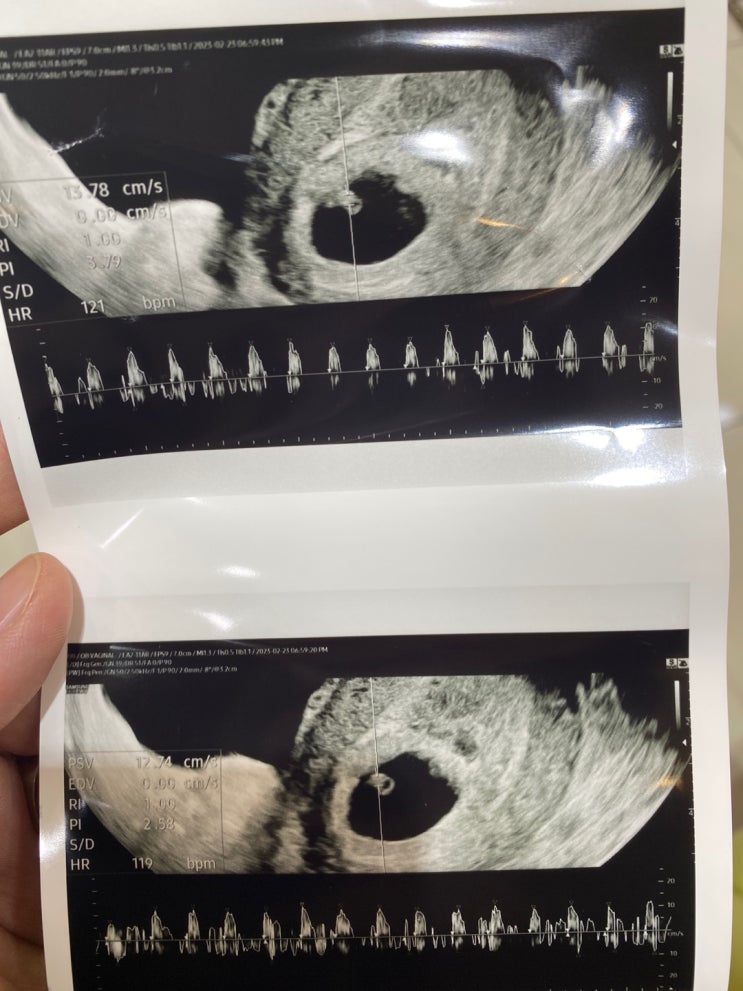

12주4일_1차 기형아검사, 성별, 목투명대검사, 입체초음파, 심장소리

오늘은 1차기형아 검사가 있는 날 기형아검사는 야간진료에는 진행하지 않아서 오후 반차를 내고 3시 40분...